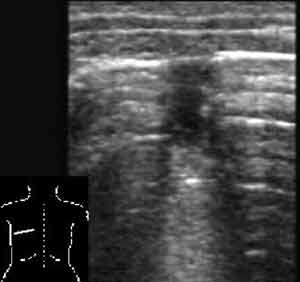

Эхография в диагностике заболеваний легких у детей.

Рис. 4. Небольшой ателектаз.

Новости лучевой диагностики 2002 1-2: 56-60